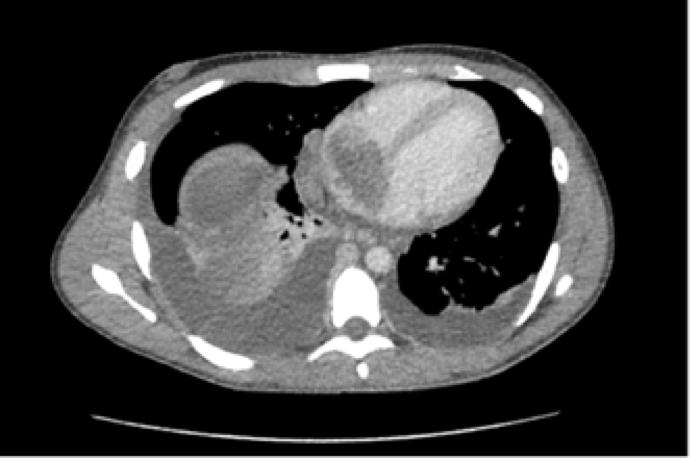

Your recommendation for management of this patient with metastatic Wilms tumor is

The next best step in management of this patient with a metastatic renal tumor is